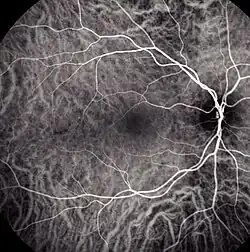

![]() Choroidal blood flow revealed with indocyanine green angiography | |

Indocyanine green angiography (ICGA) is a diagnostic procedure used to examine choroidal blood flow and associated pathology. Indocyanine green (ICG) is a water soluble cyanine dye which shows fluorescence in near-infrared (790–805 nm) range, with peak spectral absorption of 800-810 nm in blood.[1][2] The near infrared light used in ICGA penetrates ocular pigments such as melanin and xanthophyll, as well as exudates and thin layers of sub-retinal vessels.[3] Age-related macular degeneration is the third main cause of blindness worldwide, and it is the leading cause of blindness in industrialized countries.[4] Indocyanine green angiography is widely used to study choroidal neovascularization in patients with exudative age-related macular degeneration.[5] In nonexudative AMD, ICGA is used in classification of drusen and associated subretinal deposits.[5]